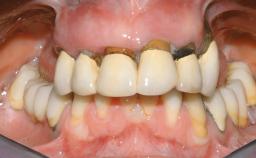

A 63-year-old male patient was referred for a consultation and treatment of partial edentulism in the maxilla. The patient presented with residual anterior teeth and declined a partial removable prosthesis. He reported that the maxillary posterior teeth had been extracted due to mobility and periodontal disease two months before the consultation. The patient’s chief complaint was that his residual maxillary teeth were mobile and that he was unable to chew. The patient’s desire was a stable and comfortable fixed maxillary rehabilitation. The patient was a light smoker (fewer than 10 cigarettes/ day), and his medical history was without significant findings. He was not on any regular medication at the time of consultation. The extraoral examination revealed a normal physiognomy with a correct distribution of the facial thirds. The patient presented a low lip line, and the transition line between teeth and soft tissues was not exposed during a forced smile.